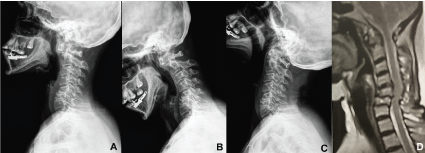

The surgical handling of subaxial disease in RA is usually performed through anterior decompression and stabilization. In specific cases where there's mobile atlantoaxial instability associated to significant subaxial disease, anterior atlantoaxial fixation avoids the morbidity of a second posterior approach. Max Aebi, et al. [31] described the atlantoaxial fixation technique through the anterior insertion of transarticular screws, providing satisfactory biomechanical results. In that way, the use of this technique allows the treatment of atlantoaxial instability and subaxial disease through a single anterior route, thus avoiding the additional damage from a posterior approach, like prone position and posterior muscle-ligament lesion. (Figure 4 and Figure 5).

Figure 4: Profile radiography (A), flexoextention radiography (B and C) and sagittal acquisition of NMR weighed in T2 (D) preoperative of a patient with RA Ranawat I, showing mobile atlantoaxial instability associated to subaxial instability with typical "staircase" malformation. View Figure 4

Figure 5: Profile radiography. (A) transoral radiography; (B) and TC with coronal reconstruction; (C) postoperative of the same patient, illustrating the surgical treatment performed with anterior trans articular atlantoaxial arthrodesis for the treatment of atlantoaxial instability associated to decompressive corpectomy with anterior arthrodesis for the treatment of subaxial instability. View Figure 5